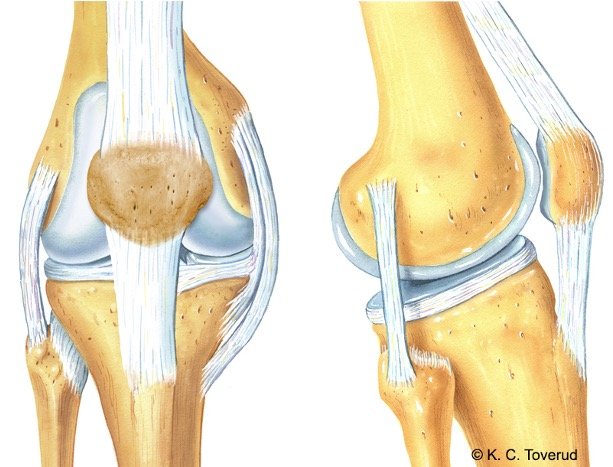

- Normal kneanatomi, akser og bevegelsesutslag.

Kne, ligamenter og muskelfester